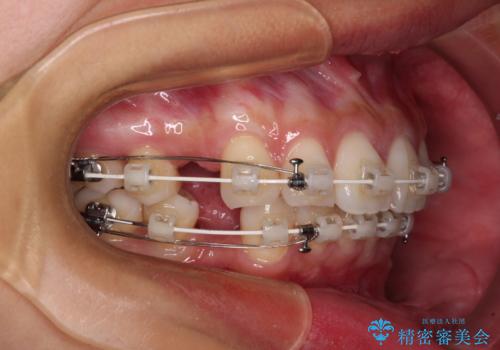

- 矯正装置

- 審美装置

結婚式を行う予定があるとのことで、表側のワイヤー装置で、速やかに治療を終えられるようにしました。

途中妊娠と出産がありましたが、予定よりも早く治療を終えることができました。